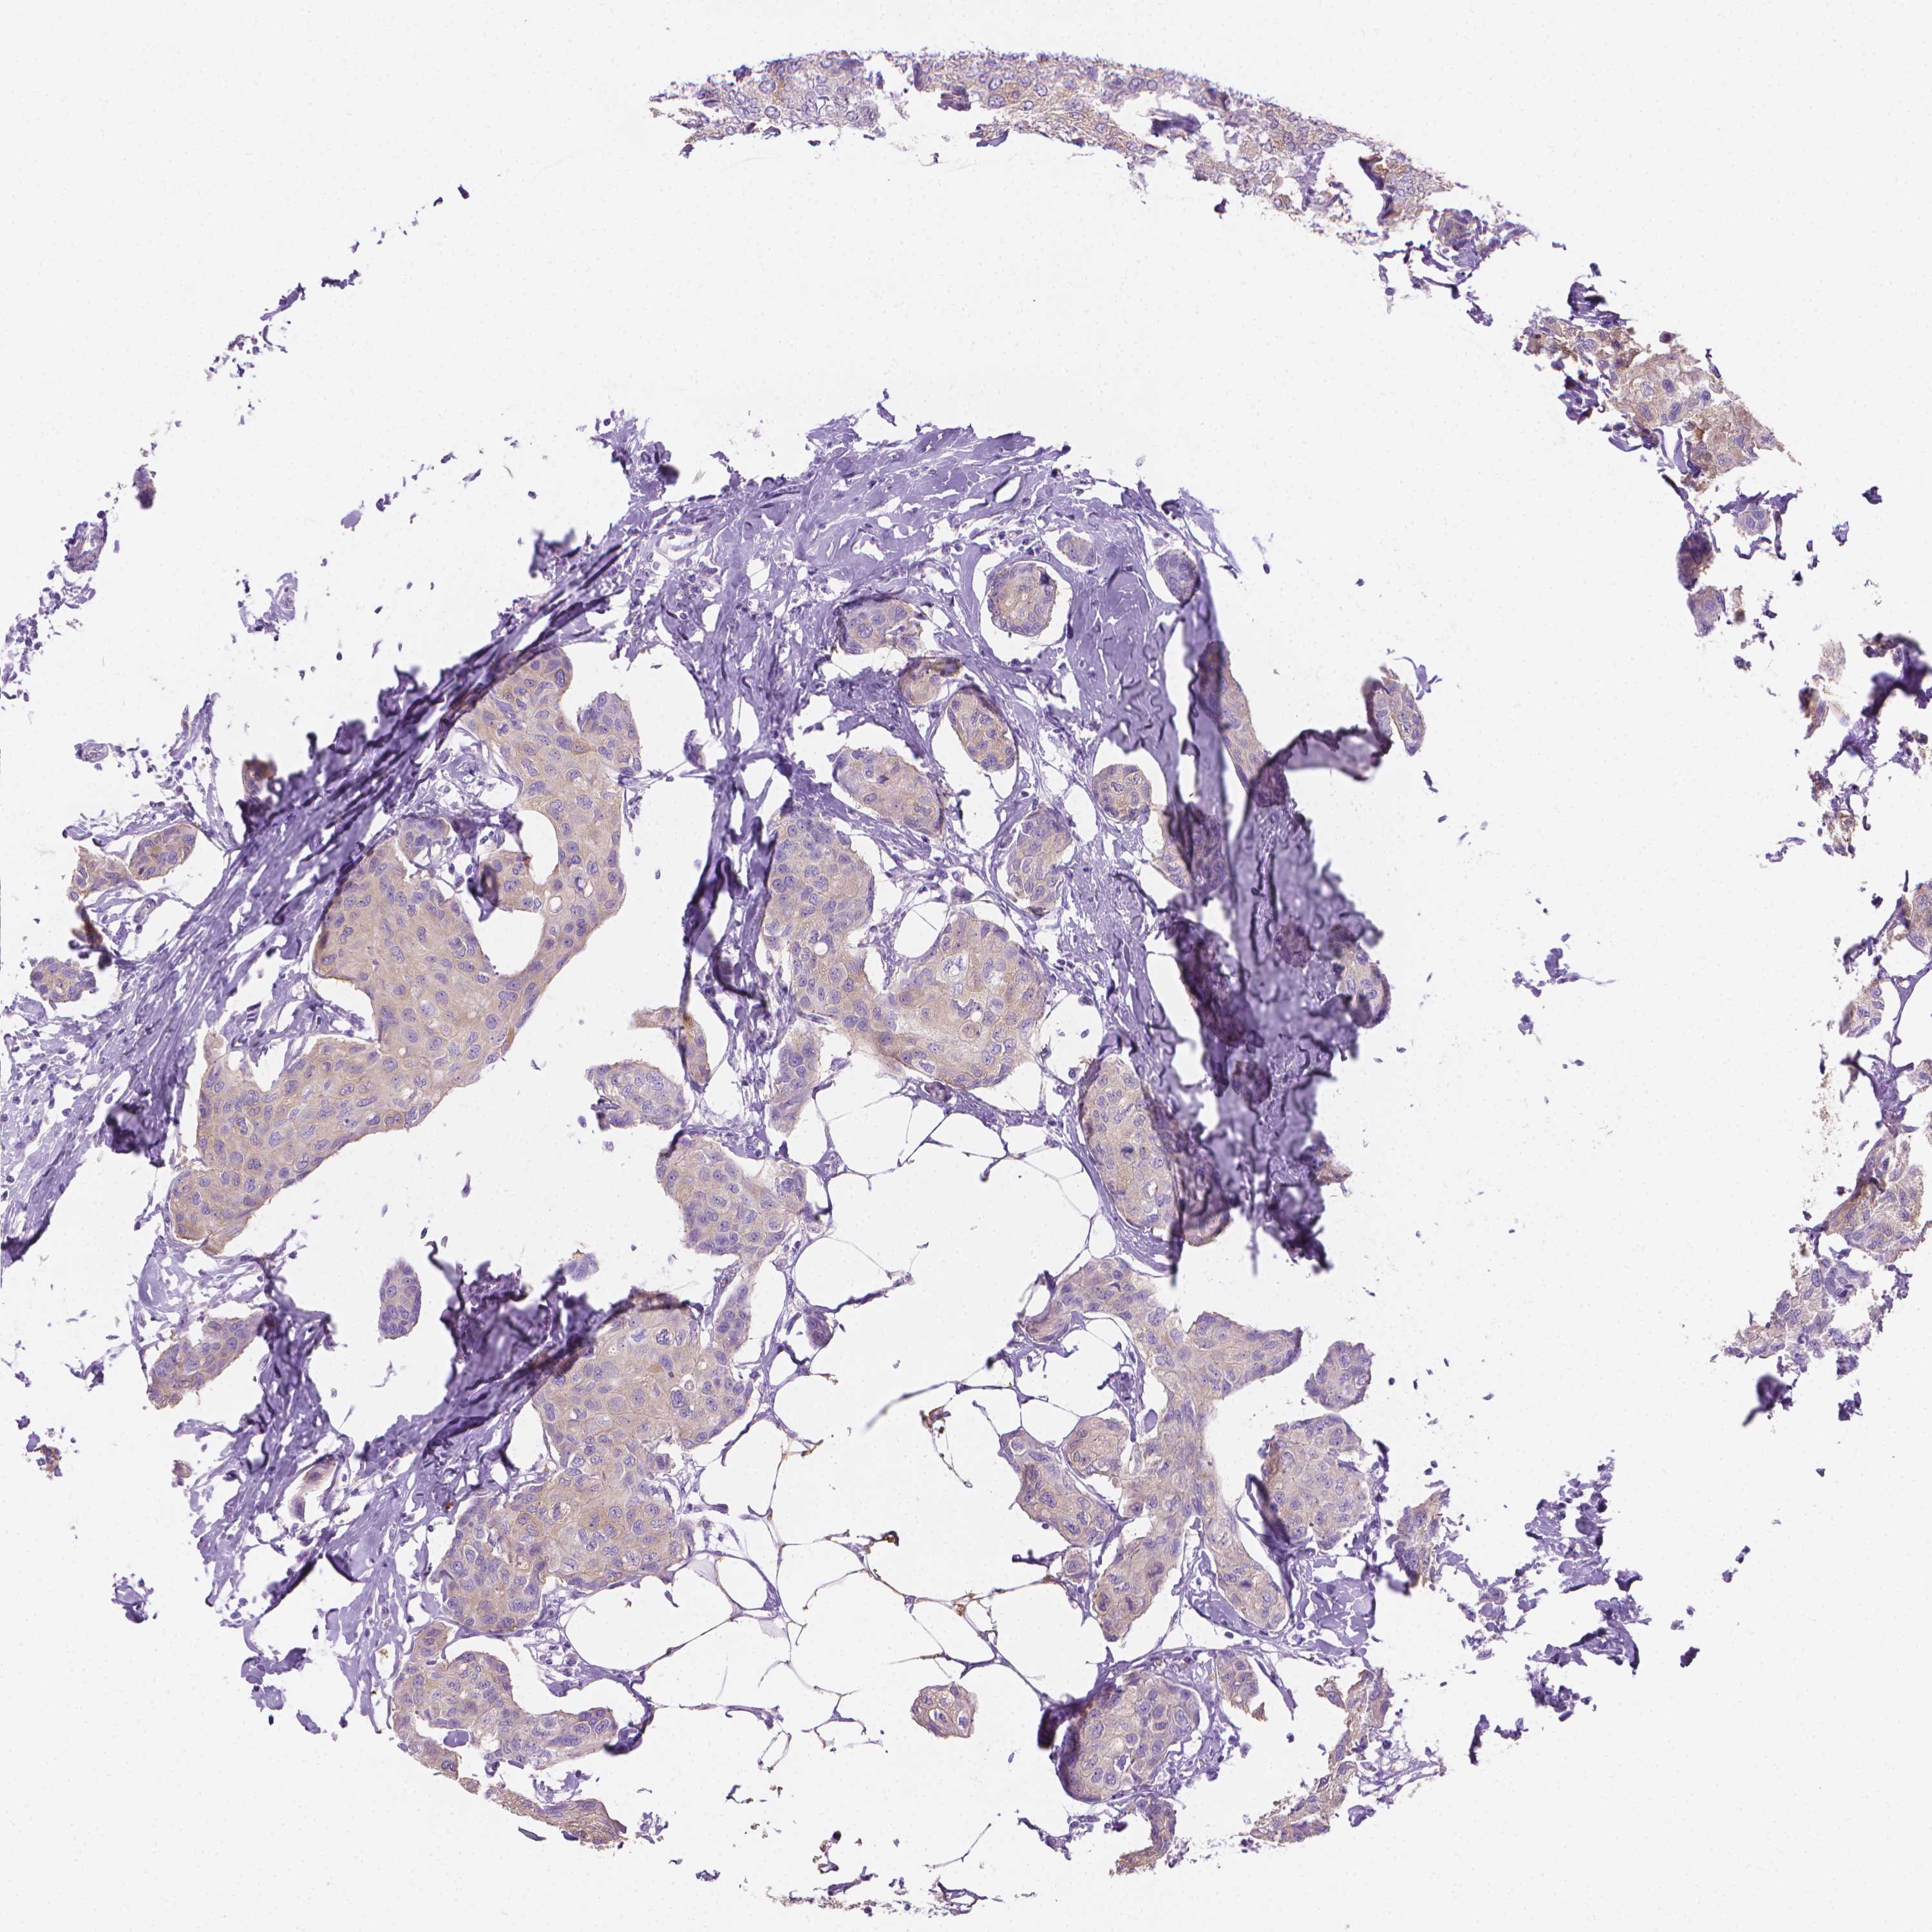

BRCA TCGA BRCA VALIDATION PROTEIN EXPRESSION